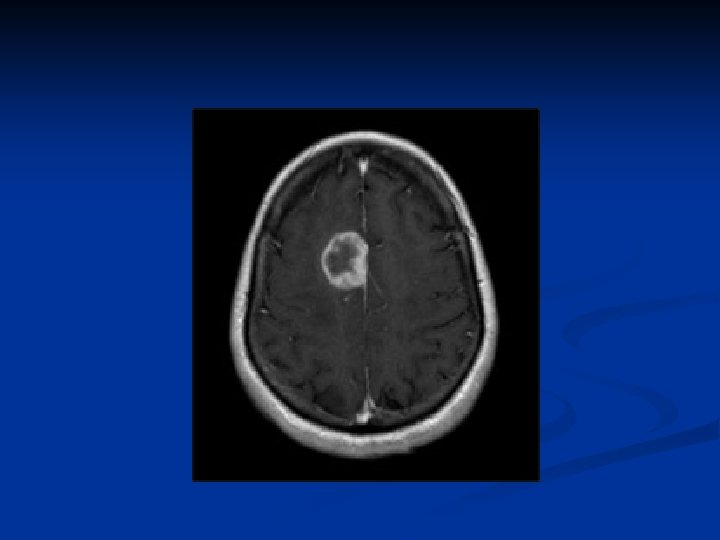

RCC with IVC thrombus